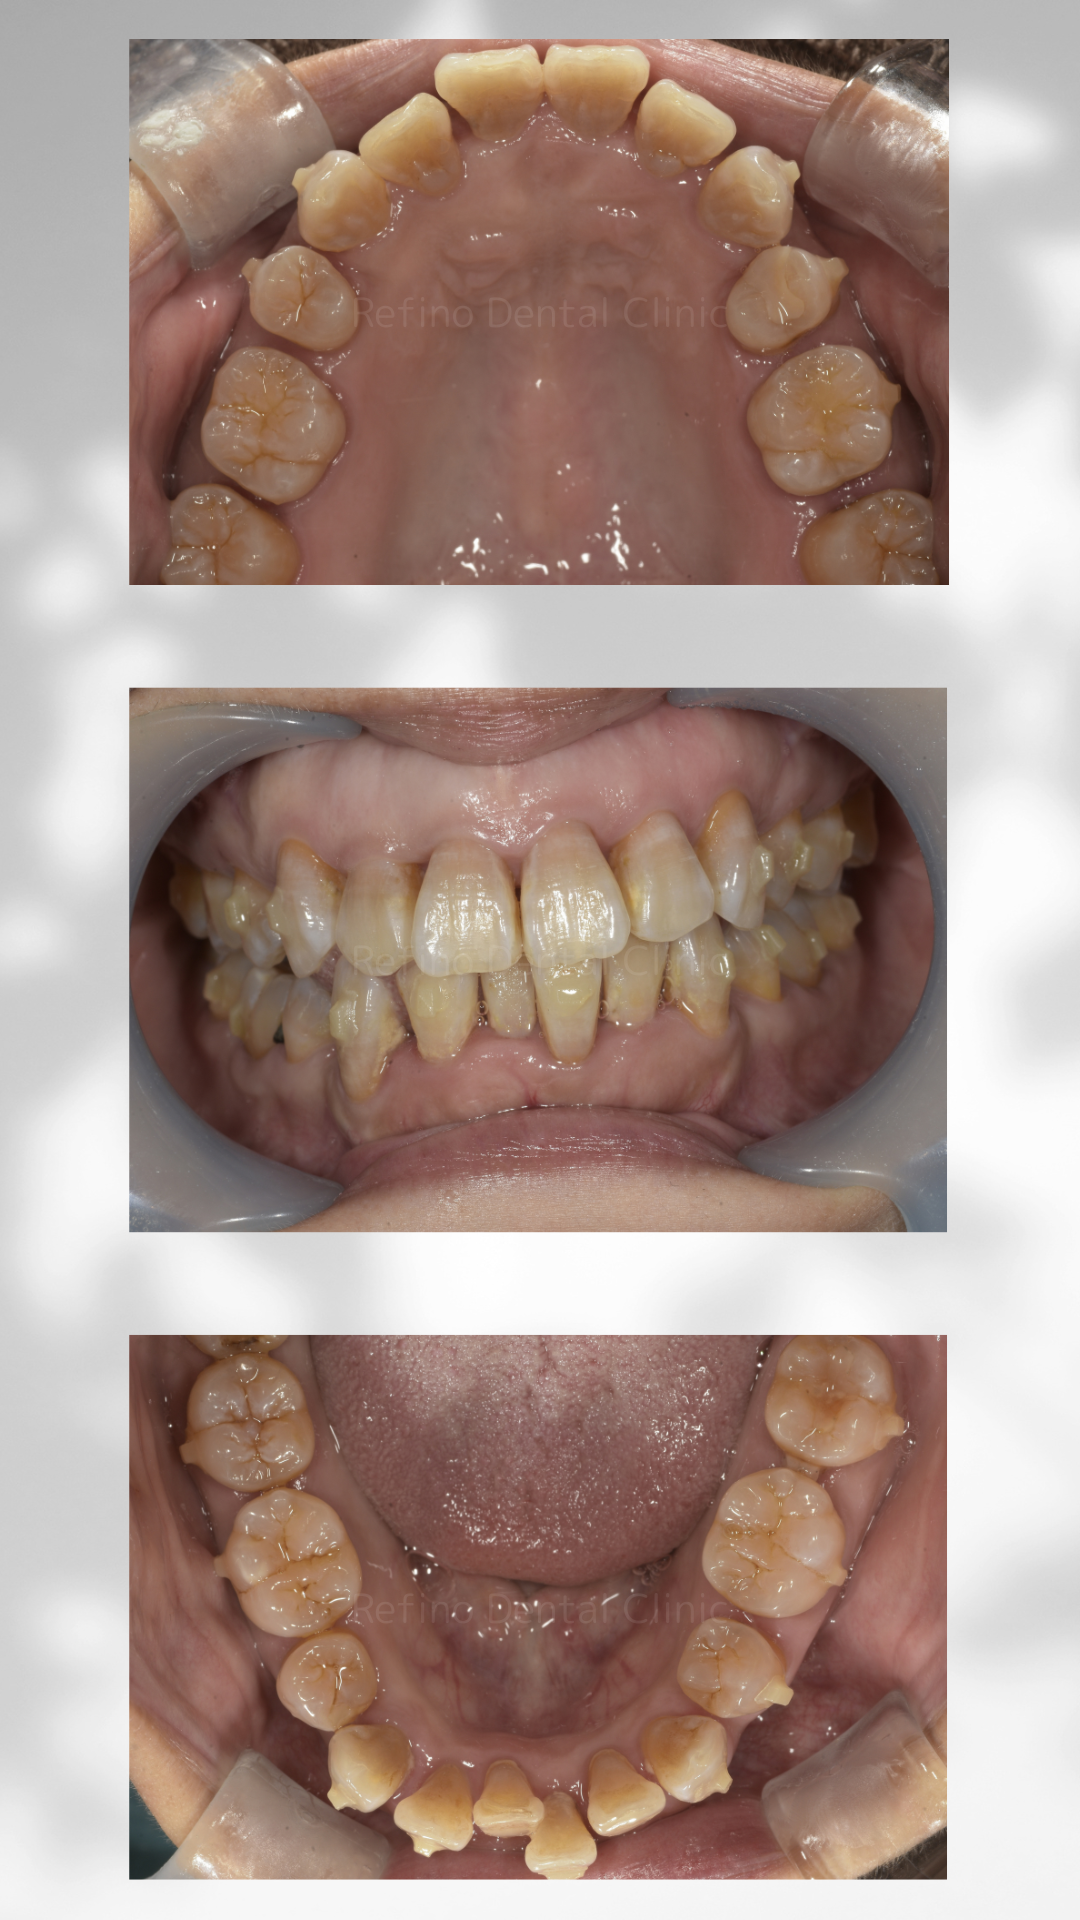

症例紹介

【治療経過】上下のガタガタ歯並びをマウスピース矯正で治療を行った症例

After

| 診断 | 上下顎叢生 | ||||

| 処置内容 | マウスピース矯正 上下顎第一小臼歯抜歯 クリアコレクト使用 |

| 通院期間 | 5ヶ月(治療途中、通院2回) | ||||